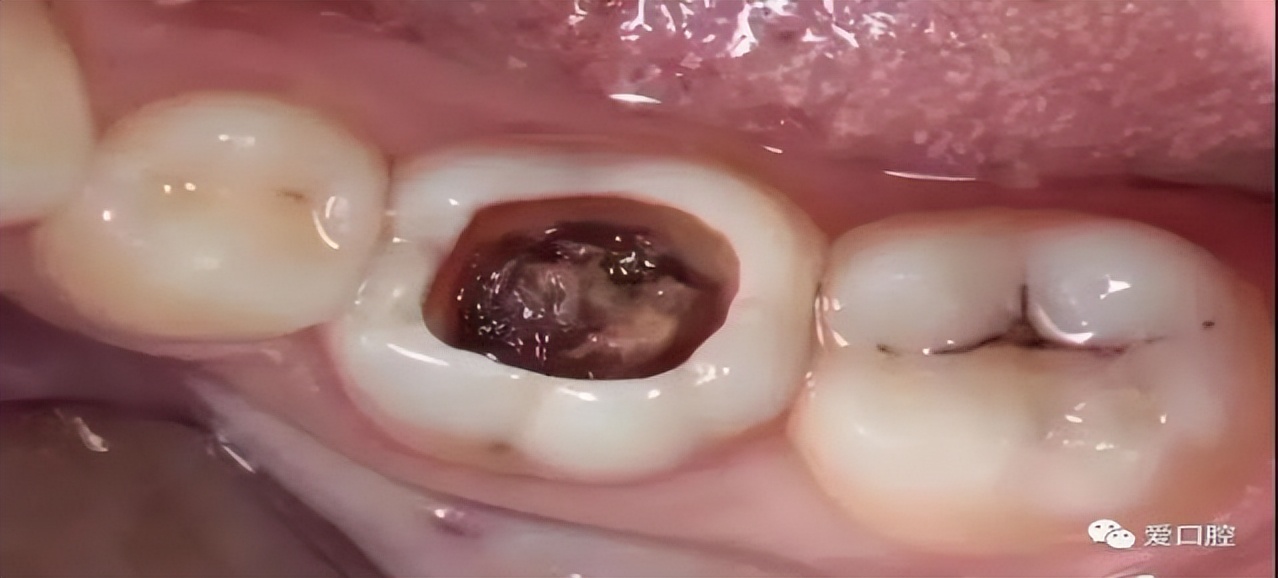

深龋

病变已达牙齿深层。一般表现为牙齿表面大而深的窝洞,或入口小而深层有较为广泛的破坏,疼痛反应较中龋严重。

这个阶段别说吃苹果了,冷热酸甜吃啥都刺激,吃啥都疼,这个时候你才会发现牙疼不是病,疼起来真要命!